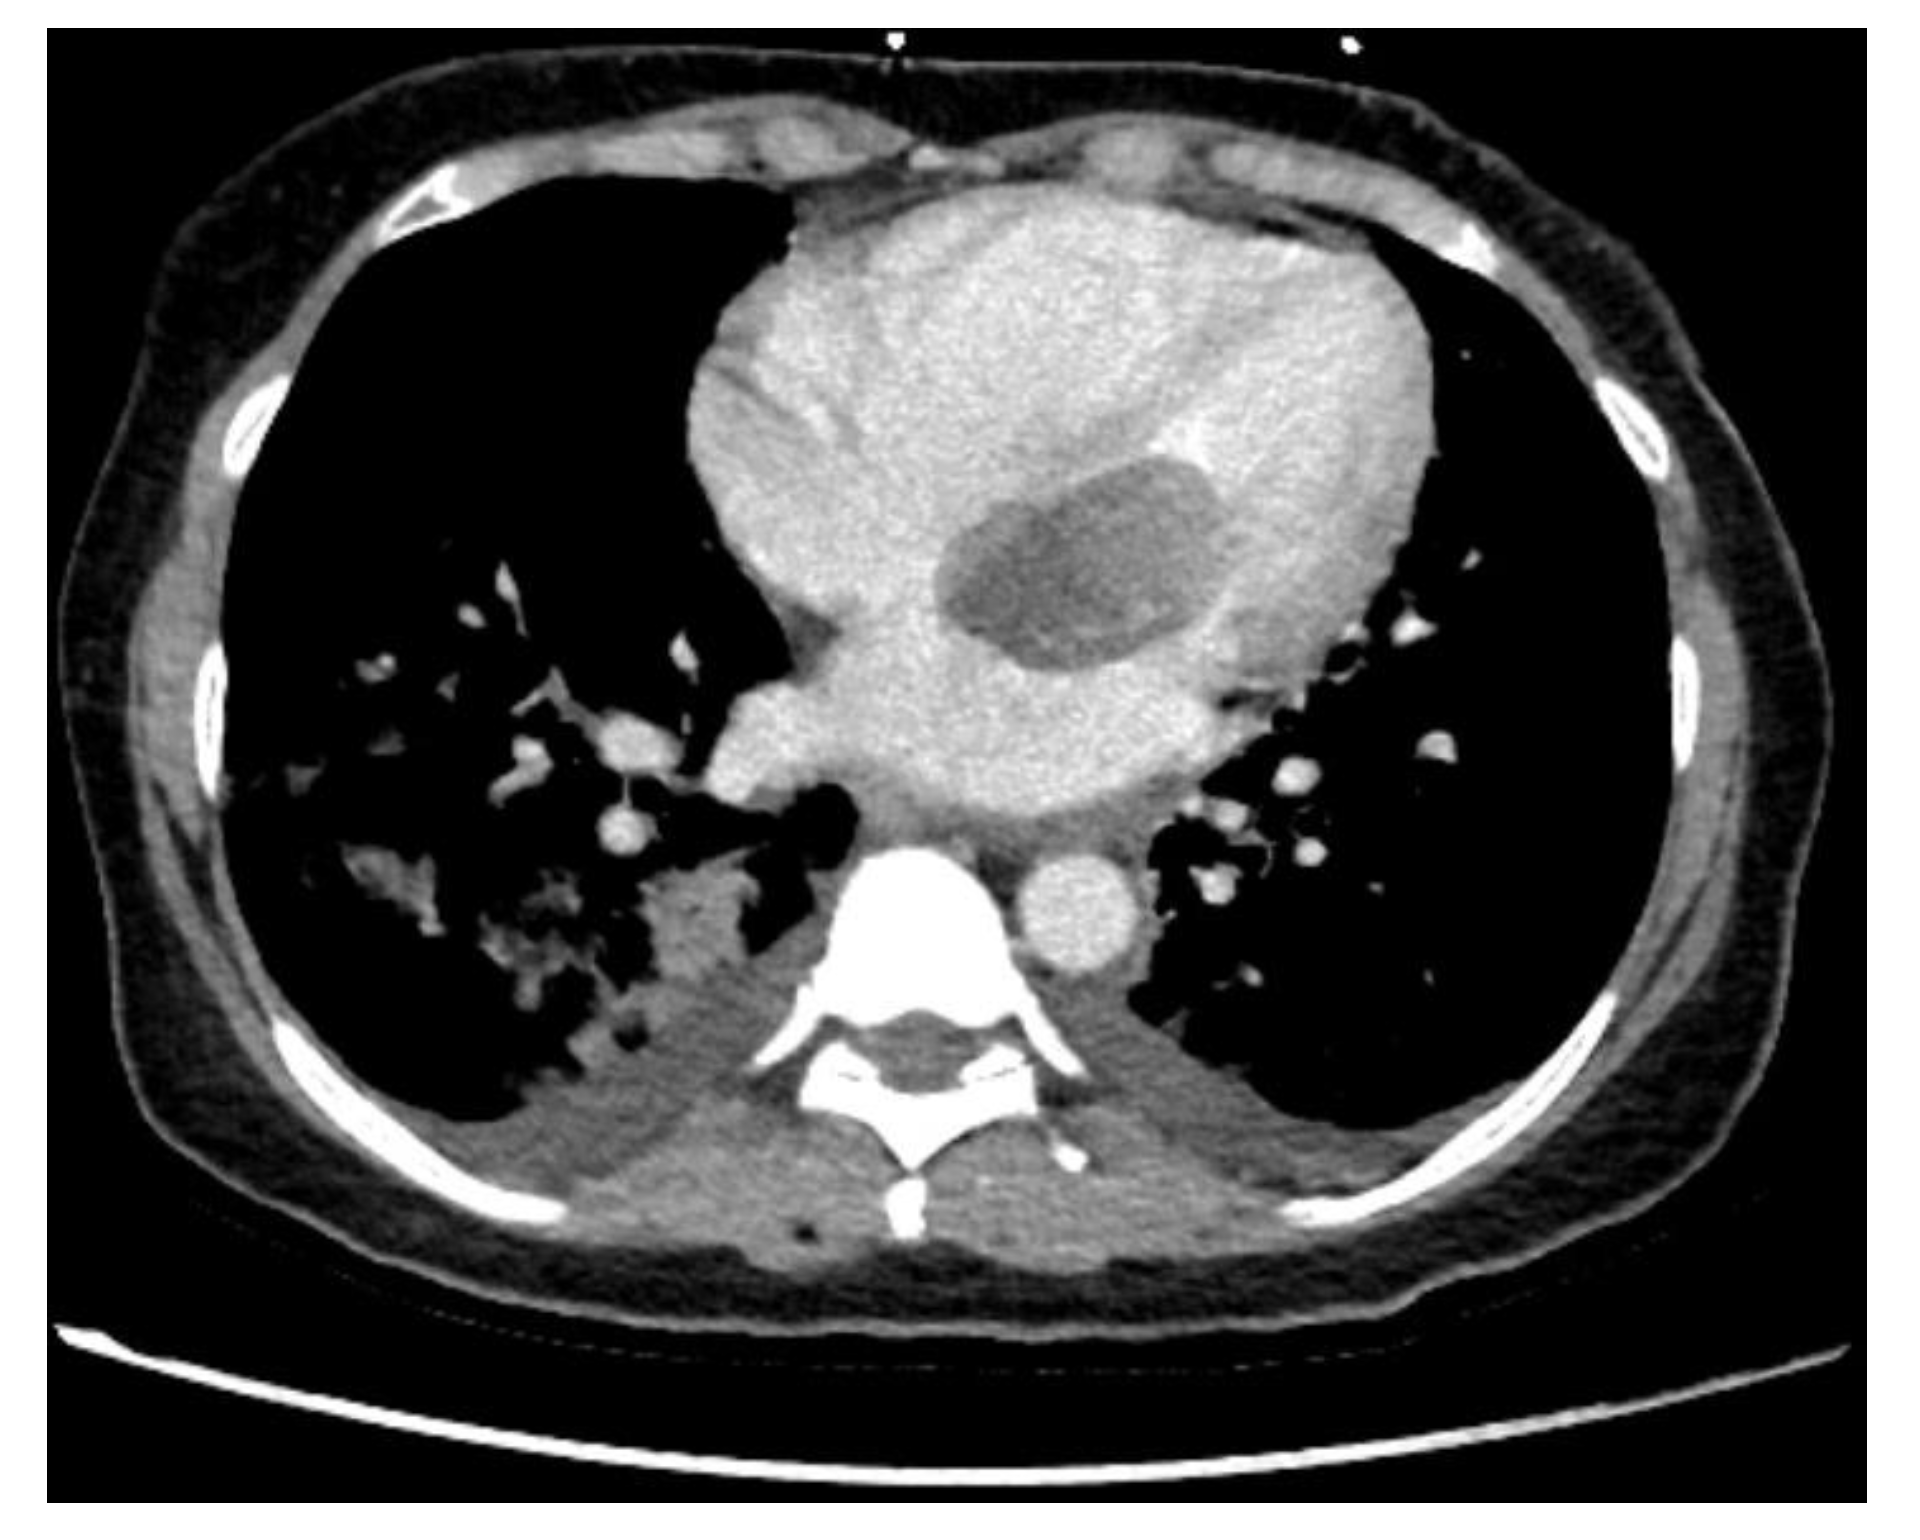

Cardiac Myxomas Resembling Malignant Neoplasia: Incidentally Diagnosed vs. Cerebral Embolized Myxomas

| Computertomography (%) | 7.1 | 15.4 | 0.671 |